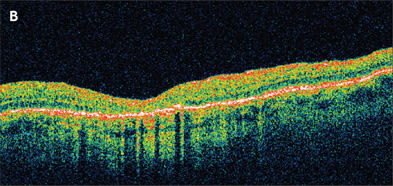

Figure 2. A. Stage 3 macular hole previtrectomy. B. Same eye 6 weeks after vitrectomy and successful closure of the macular hole.

The classification system proposed prior to the optical coherence tomography (OCT) era is still used today, and the assumed mechanism has largely been supported by findings on OCT. In summary, stage 1 holes are not true holes but rather focal areas of vitreoretinal traction. Astage 1 hole has an equal chance to recover spontaneously as it does to progress to a stage 2 hole (full-thickness hole with vitreoretinal traction on the edge of the hole)(Figure 1). Once a stage 2 hole develops, there is little chance of spontaneous recovery, and surgical intervention is considered. Stage 3 and 4 holes are full-thickness holes, with the latter associated with a posterior vitreous detachment (Figure 2). Because studies suggest that the chance of visual improvement and anatomic success is higher if the surgical repair is performed within 6 months, it should not be delayed beyond this time frame.2